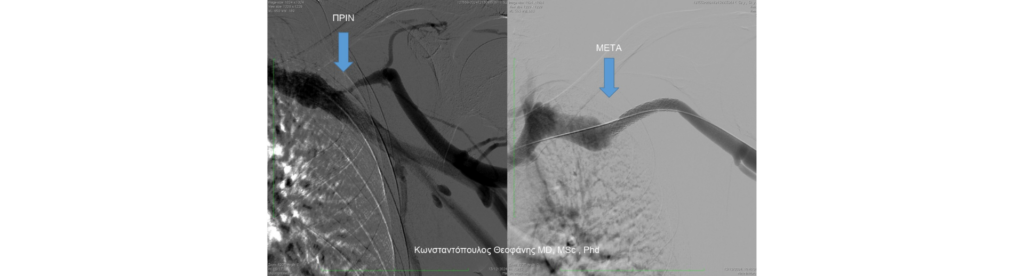

Με την αγγειοπλαστική, ο αγγειοχειρουργός εισάγει λεπτό καθετήρα με ειδικό μπαλόνι και εαν χρειαστεί επιπλέον ενδινάρθηκα (stent) στο σημείο της βλάβης και το διανοίγει, αποκαθιστώντας τη βατότητα του αγγείου. Η διαδικασία είναι ασφαλής, γρήγορη και αποτελεσματική, επιτρέποντας την άμεση επαναλειτουργία της fistula χωρίς νέα χειρουργική παρέμβαση.

Μέσω μιας μικρής βελόνας, εισάγεται λεπτός καθετήρας στο αγγείο και προωθείται μέχρι το σημείο της στένωσης ή της απόφραξης. Στη συνέχεια, τοποθετείται ειδικό μπαλόνι το οποίο διαστέλλεται ελεγχόμενα, ασκώντας πίεση στα τοιχώματα του αγγείου. Με αυτόν τον τρόπο, η στένωση διανοίγεται και αποκαθίσταται η φυσιολογική ροή του αίματος μέσα στη fistula. Σε ανθεκτικές βλάβες και για αποφυγή επαναστένωσης, ακολουθεί διαστολή του αγγείου με αεροθάλαμο επικαλυμμένο με κυτταροστατικό φάρμακο (πακλιταξέλη) που εξασφαλίζει πολύ καλό αποτέλεσμα ως προς τη βατότητα.

Σε περιπτώσεις όπου η στένωση είναι εκτεταμένη ή επαναλαμβανόμενη, μπορεί να χρησιμοποιηθεί ενδοαυλικό stent ή stent-graft. Με αυτόν τον τρόπο μπορεί να διατηρηθεί η βατότητα του αγγείου και να αποτραπεί νέα απόφραξη.